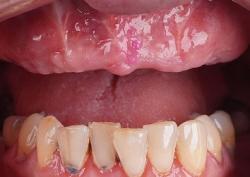

Людмила, 59 лет

Жалобы пациента:

Из-за длительного отсутствия зубов пациентку стало беспокоить постепенное смещение оставшихся зубов, что вызывало неприятные ощущения при смыкании челюстей. Дополнительно её беспокоила эстетическая сторона вопроса – отсутствие зубов вызывало психологический дискомфорт и заставляло сдерживать улыбку.

Что делали:

Результат:

Полностью восстановлена жевательная функция, зубной ряд обрёл естественный внешний вид, предотвращено дальнейшее смещение зубов.